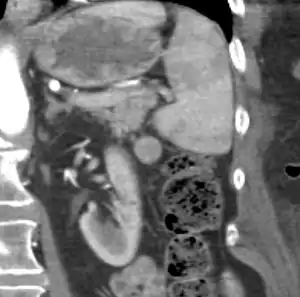

| CT scan of an accessory spleen (in center of image) between the spleen and left kidney. | |

If splenectomy is performed for conditions in which blood cells are sequestered in the spleen, failure to remove accessory spleens may result in the failure of the condition to resolve.[1] During medical imaging, accessory spleens may be confused for enlarged lymph nodes or neoplastic growth in the tail of the pancreas,[5] gastrointestinal tract, adrenal glands or gonads.[2]